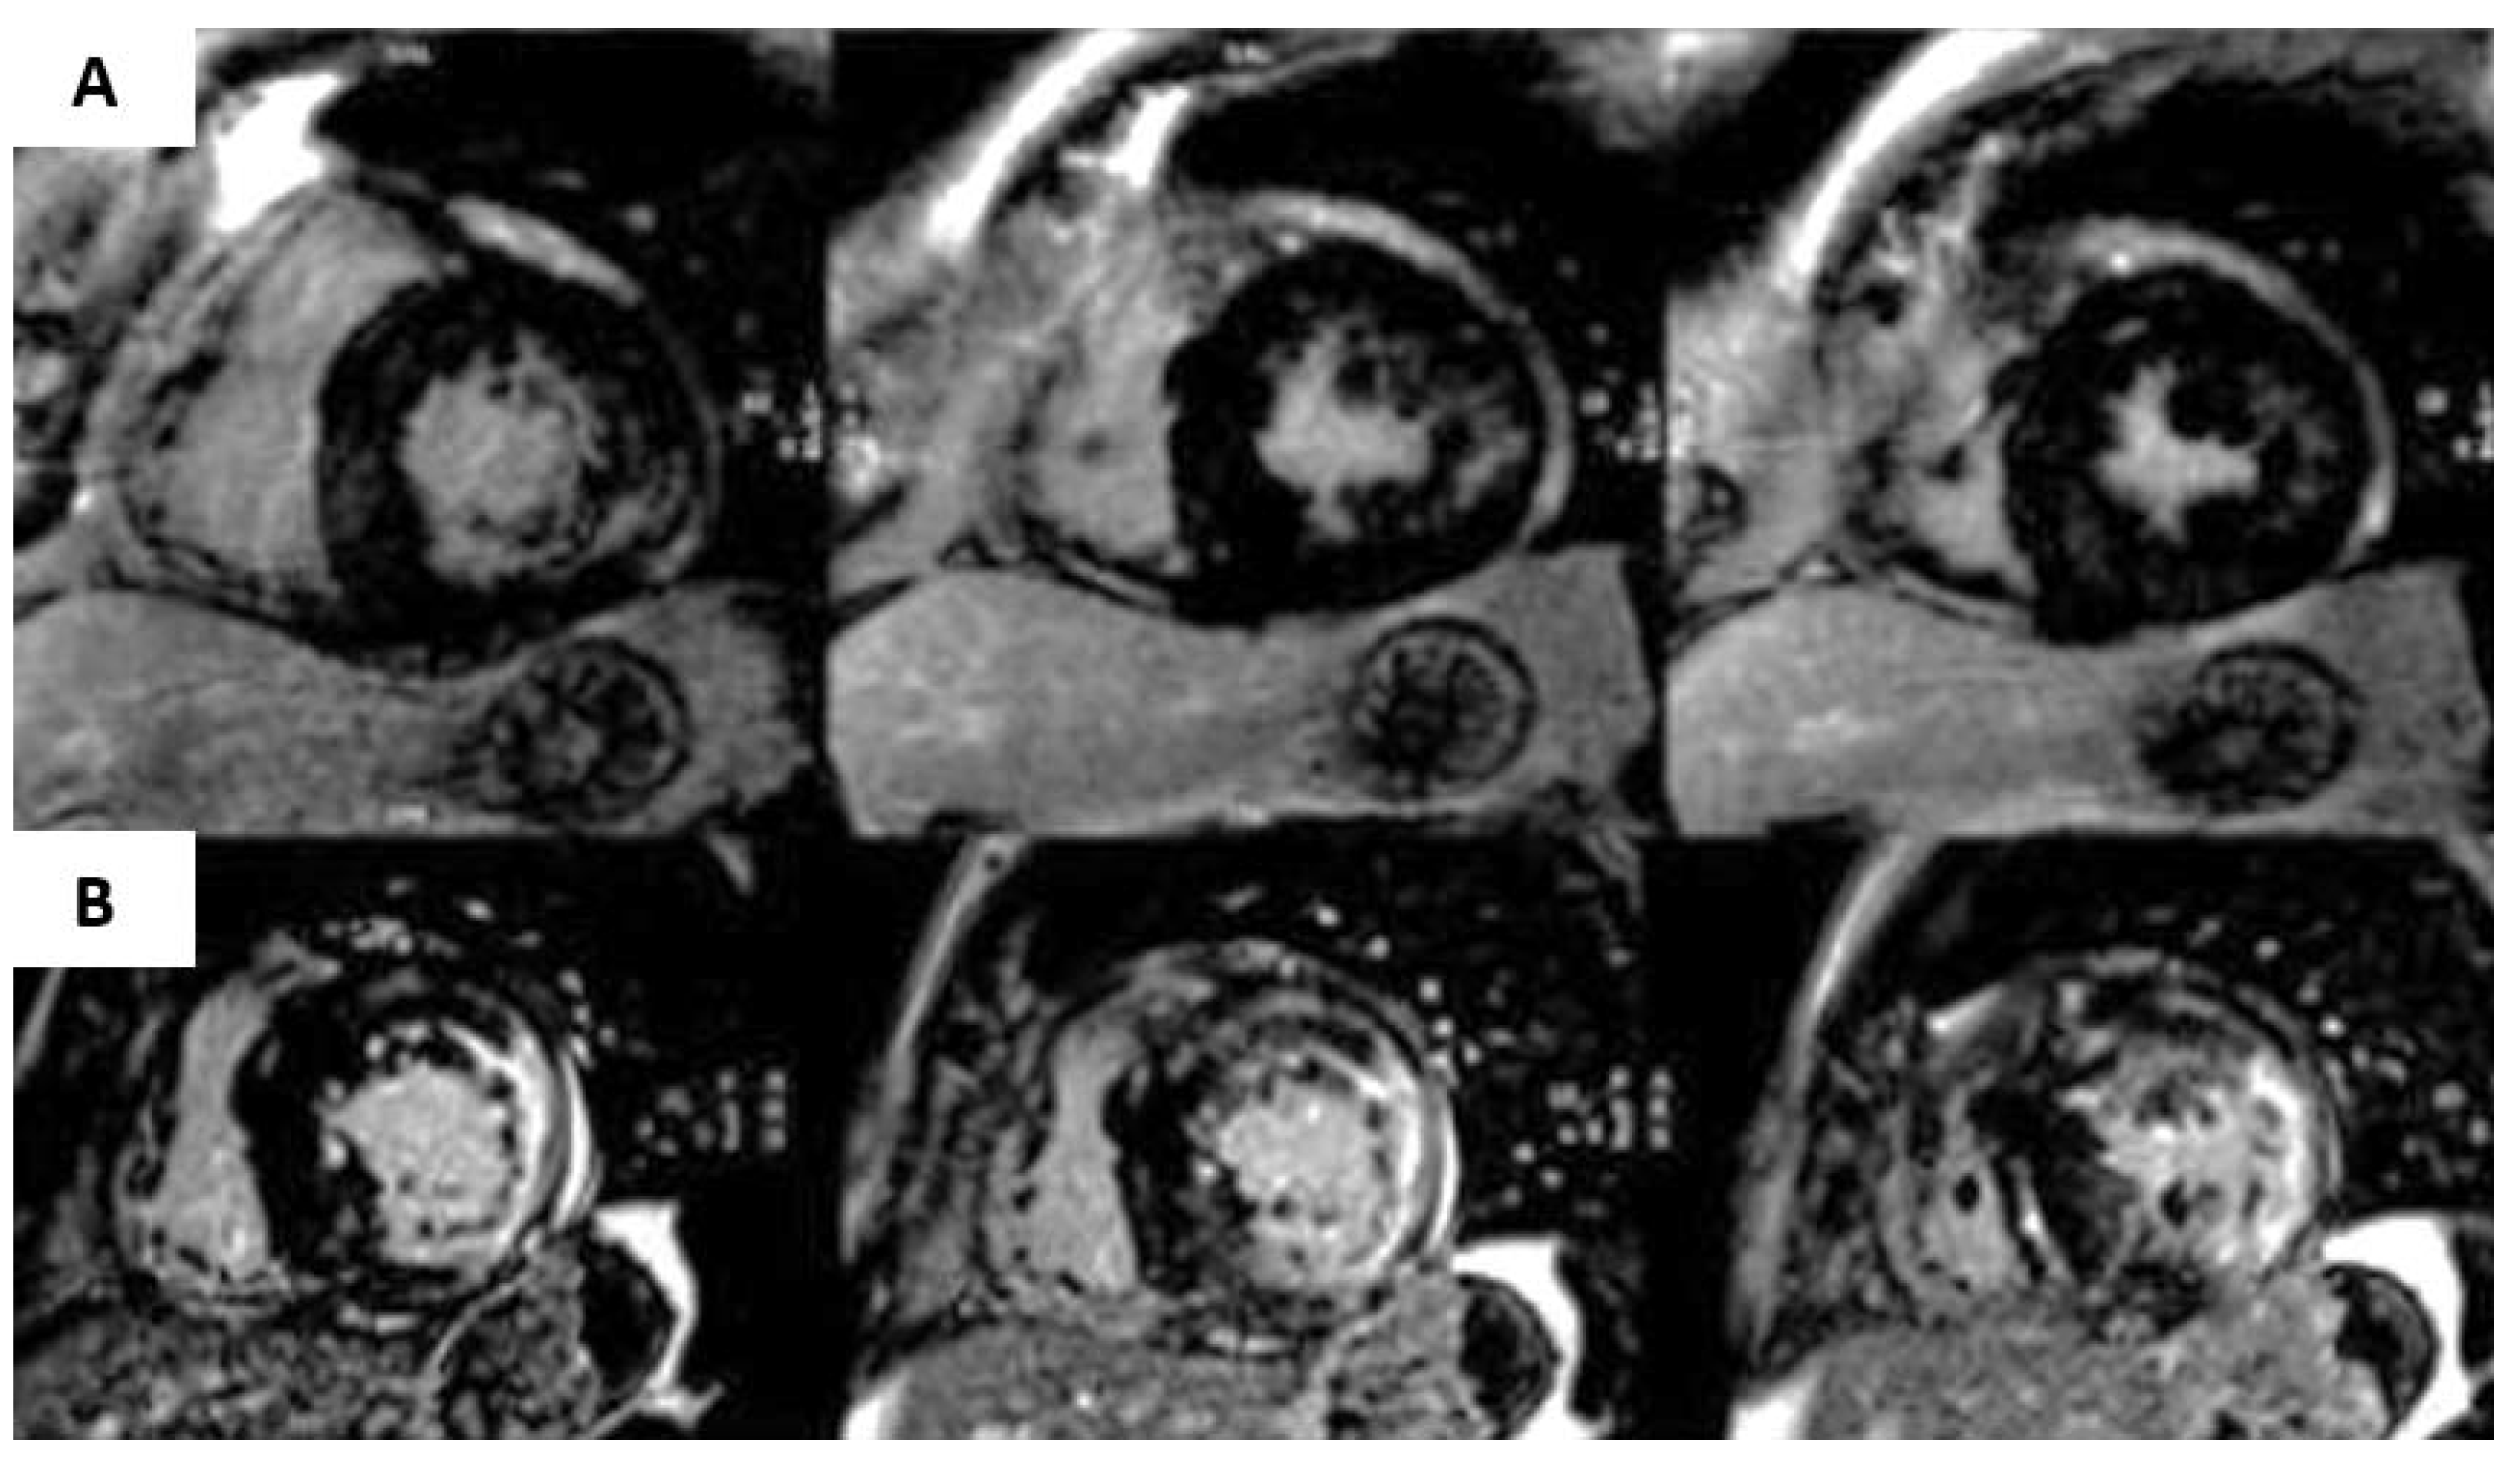

4.5. Cardiac Sarcoidosis

- Vita, T.; Okada, D.R.; Veillet-Chowdhury, M.; Bravo, P.E.; Mullins, E.; Hulten, E.; Agrawal, M.; Madan, R.; Taqueti, V.R.; Steigner, M.; et al. Complementary Value of Cardiac Magnetic Resonance Imaging and Positron Emission Tomography/Computed Tomography in the Assessment of Cardiac Sarcoidosis. Circ. Cardiovasc. Imaging 2018, 11, e007030. [Google Scholar] [CrossRef]

- Youssef, G.; Leung, E.; Mylonas, I.; Nery, P.; Williams, K.; Wisenberg, G.; Gulenchyn, K.Y.; Dekemp, R.A.; DaSilva, J.; Birnie, D.; et al. The Use of 18F-FDG PET in the Diagnosis of Cardiac Sarcoidosis: A Systematic Review and Metaanalysis Including the Ontario Experience. J. Nucl. Med. 2012, 53, 241–248. [Google Scholar] [CrossRef] [Green Version]

- Blankstein, R.; Osborne, M.; Naya, M.; Waller, A.; Kim, C.K.; Murthy, V.; Kazemian, P.; Kwong, R.Y.; Tokuda, M.; Skali, H.; et al. Cardiac Positron Emission Tomography Enhances Prognostic Assessments of Patients With Suspected Cardiac Sarcoidosis. J. Am. Coll. Cardiol. 2014, 63, 329–336. [Google Scholar] [CrossRef] [Green Version]

- Dweck, M.; Abgral, R.; Trivieri, M.G.; Robson, P.M.; Karakatsanis, N.; Mani, V.; Palmisano, A.; Miller, M.A.; Lala, A.; Chang, H.L.; et al. Hybrid Magnetic Resonance Imaging and Positron Emission Tomography With Fluorodeoxyglucose to Diagnose Active Cardiac Sarcoidosis. JACC Cardiovasc. Imaging 2018, 11, 94–107. [Google Scholar] [CrossRef]